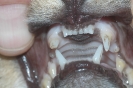

Gebiss-Fehlstellungen

(6 pictures)

Galerie